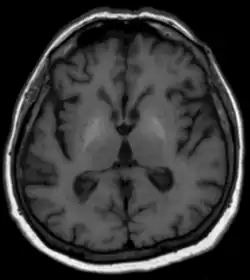

Les méthodes habituelles telles qu'analyses de sang, échographie et autres procédures d'imagerie par tomographie ainsi que la clinique[1] et, si nécessaire, une biopsie du foie avec examen histologique, sont disponibles pour diagnostiquer la maladie hépatique sous-jacente. En ce qui concerne la dégénérescence du cerveau, aucun changement n'est généralement visible sur la tomodensitométrie. L'IRM montre généralement une augmentation du signal dans les noyaux gris centraux sur les séquences natives pondérées en T1[1]. On soupçonne que la cause en est des dépôts de minéraux paramagnétiques, potentiellement réversibles après une transplantation hépatique[1],[2]. Les images pondérées T2 ne montrent généralement aucune anomalie. En termes de diagnostic différentiel, les changements de signal décrits ci-dessus sont parfois observés avec une nutrition parentérale à long terme mais également avec des calcifications idiopathiques. La maladie de Wilson doit également être prise en compte dans le diagnostic différentiel[1].